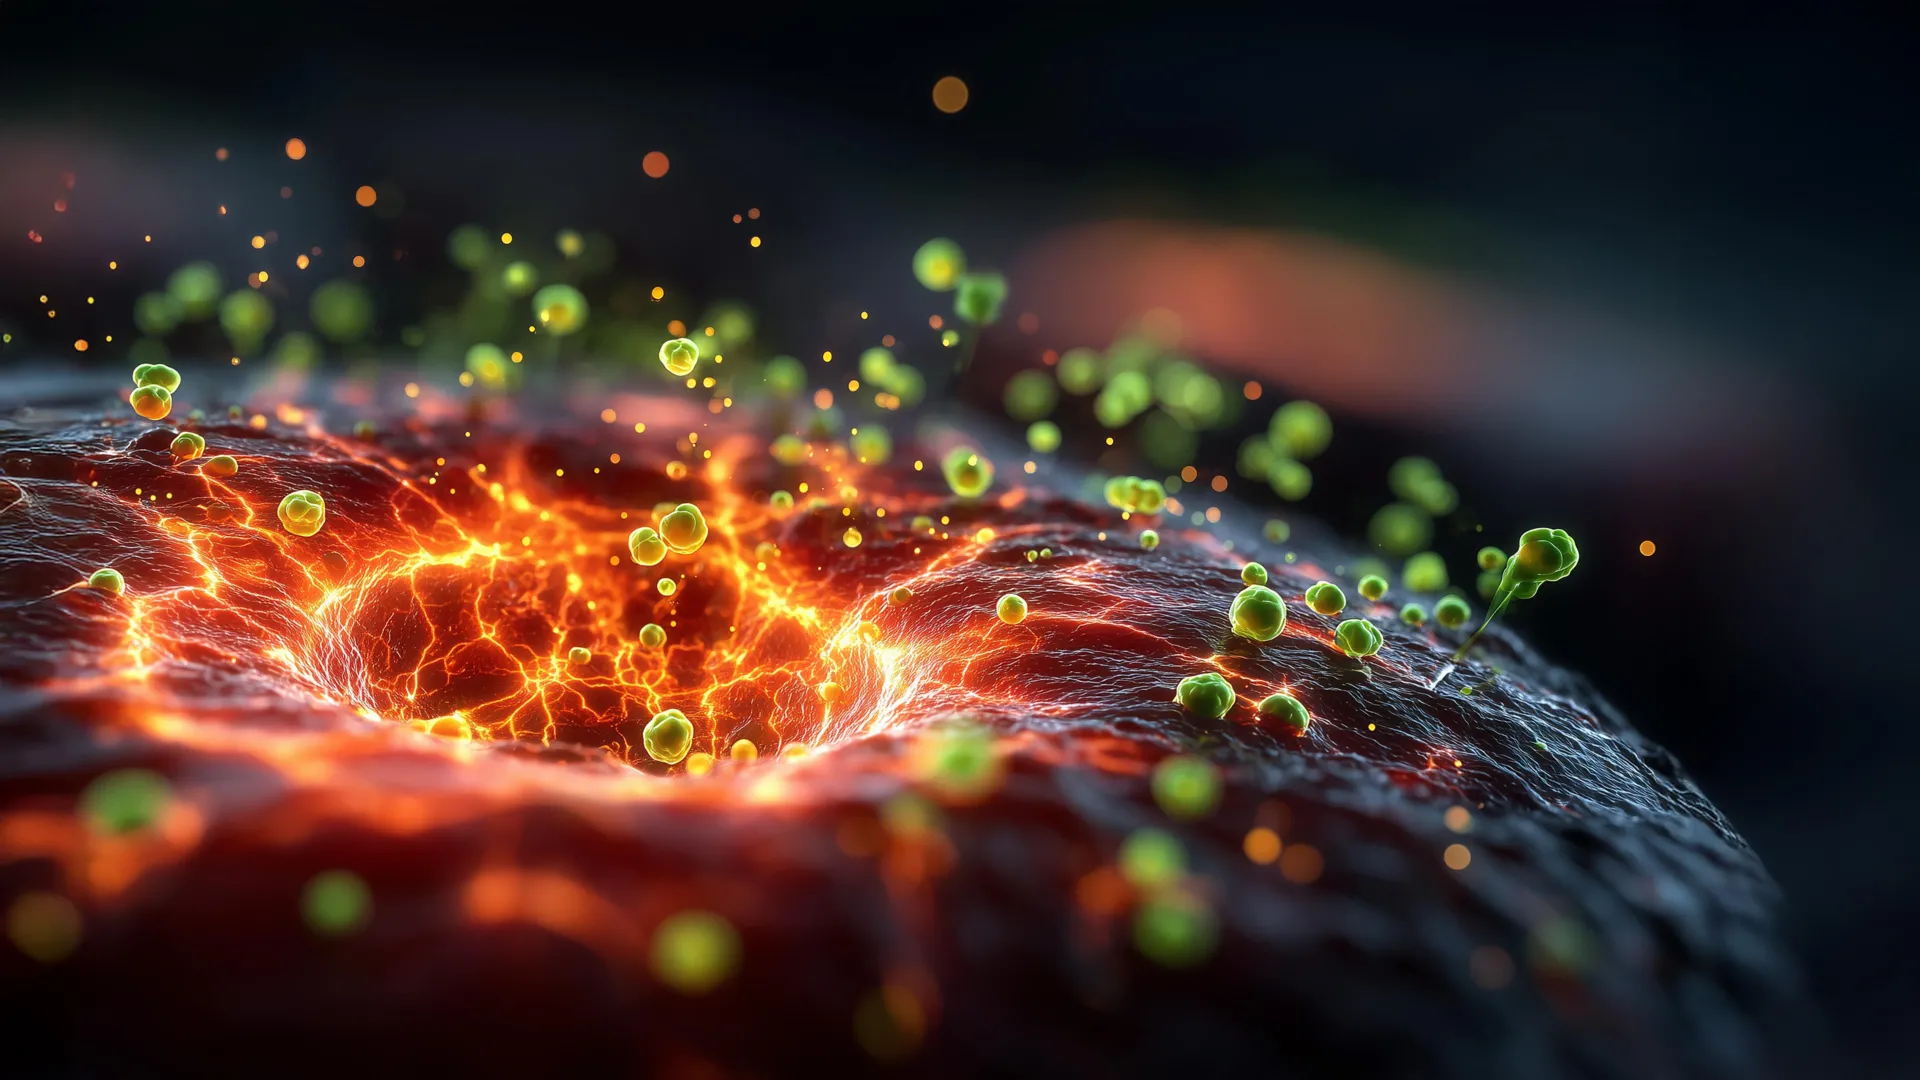

Scientists engineer bacteria to eat cancer tumors from the inside out - ScienceDaily

Researchers are engineering bacteria to invade tumors and consume them from the inside. Because tumor cores lack oxygen, they’re the perfect breeding ground for these microbes. The team added a genetic tweak that helps the bacteria survive longer near oxygen-…